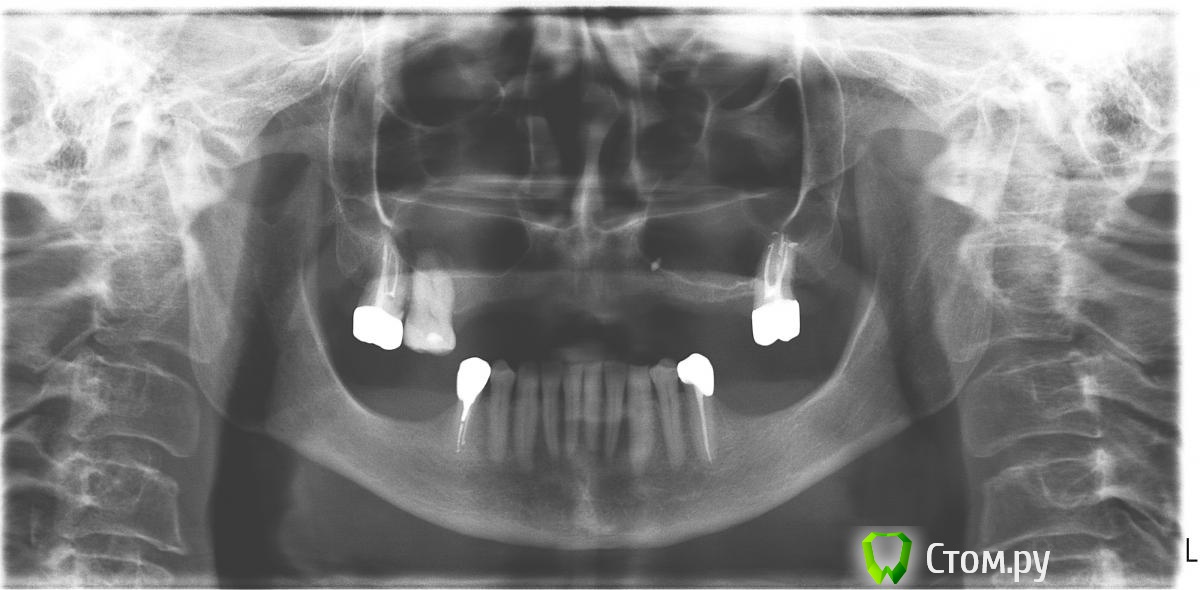

artem29 Опубликовано 19 октября, 2014 Поделиться Опубликовано 19 октября, 2014 (изменено) Уважаемые доктора, поделитесь, пожалуйста, опытом. Есть пациентка, возраст после 40 лет. Желает избавится от частично съёмных протезов, заменить их несъёмными. КТ будет чуть позже.Я (как хирург) могу предположить, что установка имплантатов в позиции 5-5 и 2-2, ждём пока интегрируют и затем балочная конструкция.Перед установкой имплантатов провести синуслифтинг, либо совместить аугментацию и установку имплантатов (решится в процессе синуслифтинга). Слева по типу латерального окна, а справа, возможно, достаточно будет и закрытого. Какую бы тактику спланировали вы на верхней и на нижней челюсти и какой длины имплантаты для верхней челюсти взяли?система: Dentium: SuperLine. Заранее всем благодарен. Изменено 19 октября, 2014 пользователем artem29 Ссылка на комментарий

artem29 Опубликовано 25 октября, 2014 Автор Поделиться Опубликовано 25 октября, 2014 Вот результаты КТ. Воскового планирования пока не было. Сразу несколько вопросов к тему у кого был подобный опыт работ.1. что с инородным телом во 2-ом сегменте? обойти при синуслифтинге, не трогать ту зону с инородным телом или постараться убрать? может нужен лор?2. будут ли состоятельны имплантаты размером 4,5х6,0 в позициях 3.6, 3.7 после нагрузки или нужно проводить аугментацию и ставить имплантаты большего размера? 3. в 4 сегменте предпочтительная аугментация сэндвич-техникой?1 сегмент_1.bmp1 сегмент_2.bmp1 сегмент_3.bmp2 сегмент_1.bmp2 сегмент_2.bmp2 сегмент_3.bmp3 сегмент_1.bmp3 сегмент_2.bmp3 сегмент_3(36).bmp3 сегмент_3(37).bmp Ссылка на комментарий